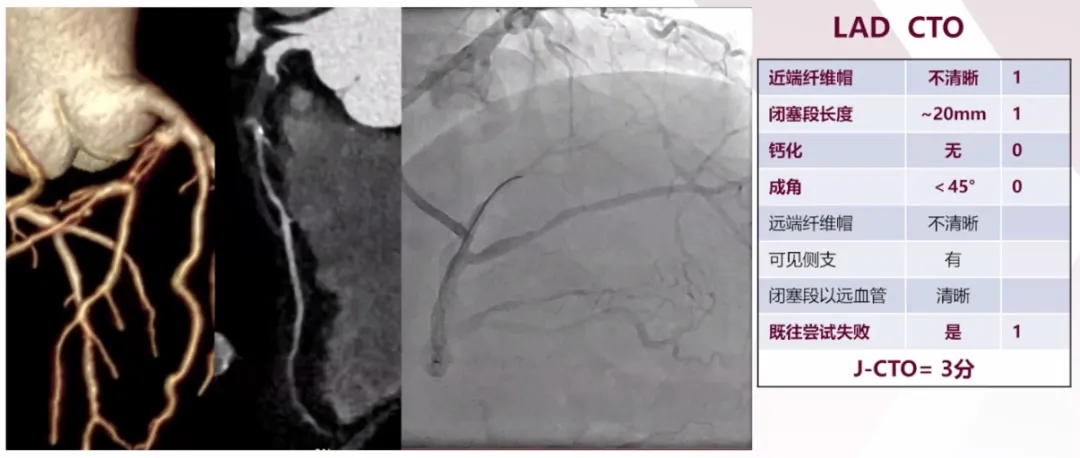

➤双侧冠状动脉造影评估LAD闭塞情况

➤冠脉CTA提示:LAD闭塞段较长约20mm,近端纤维帽不清晰,无明显钙化、成角,右冠后降支通过间隔支为LAD提供侧支循环。结合既往正向开通尝试失败等综合评估,该患者LAD CTO的J-CTO评分为3分,前向导丝开通难度较大。